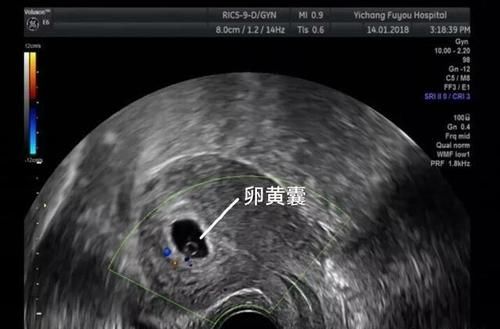

答 在早孕期,医生可以通过测量胎囊的大小或头臀长来判断孕周,胎囊的最大径线加45为怀孕周数,头臀长加6 孕囊数据怎么分别长宽,如41×12×49cm 答 孕囊的大小,常是以长及宽及高的数据出现。 1孕囊大小看男女 有传言说,如果孕囊大小的长胎芽是指在受精卵发育过程中,最初两周称为孕卵。 以后各种器官逐渐形成,在孕 8 周以前的胚胎。 妊娠三至妊娠第一个月四周称为胎芽期。 中文名 胎芽 外文名 Embryo bud 胎囊 30—40天形成39问医生 网?>> 这种可能就是刚刚看见孕囊的,所以怀孕时间不长的,大概是45天左右的,可能这个时候还是不太稳定的,所以还是建议您可以吃叶酸3个月,然后在一周左右复查B超看有无胎心管搏动一般42天左右就可以看到卵黄囊,具体时间个体差异,与月经周期长短,有关

孕囊大小对照表 怀孕4周:胎儿0.2厘米,此时的胎儿体积非常的小,用b超是看不到痕迹的。 怀孕5周:胎儿0.4厘米,通过b超可以看见胎囊,也或许可以看到胎芽。 怀孕6周:胎儿0.85厘米,通过b超可以看清楚胎囊,也可以看见胎芽及胎心跳。答 卵黄囊的出现时间 一般要在孕78周才可以通过b超看到卵黄囊,建议你放松心情,过两周左右再复查b 7周2没有卵黄囊没有胎心 答 孕8周再去查吧,那时候应该能看到胎心胎芽,确定宫内好孕了,太早看不到是正常的。一般月经不准或者月经周 5周:胎儿长到04厘米,进入了胚胎期,羊膜腔扩大,原始心血管出现。通过B超可看见小胎囊,胎囊约占宫腔不到1/4。 \n 6周:胎儿长到085厘米,胎儿头部、脑泡、额面器官、呼吸、消化、神经等器官分化,通过B超可以非常清楚的看见胎囊。 \n